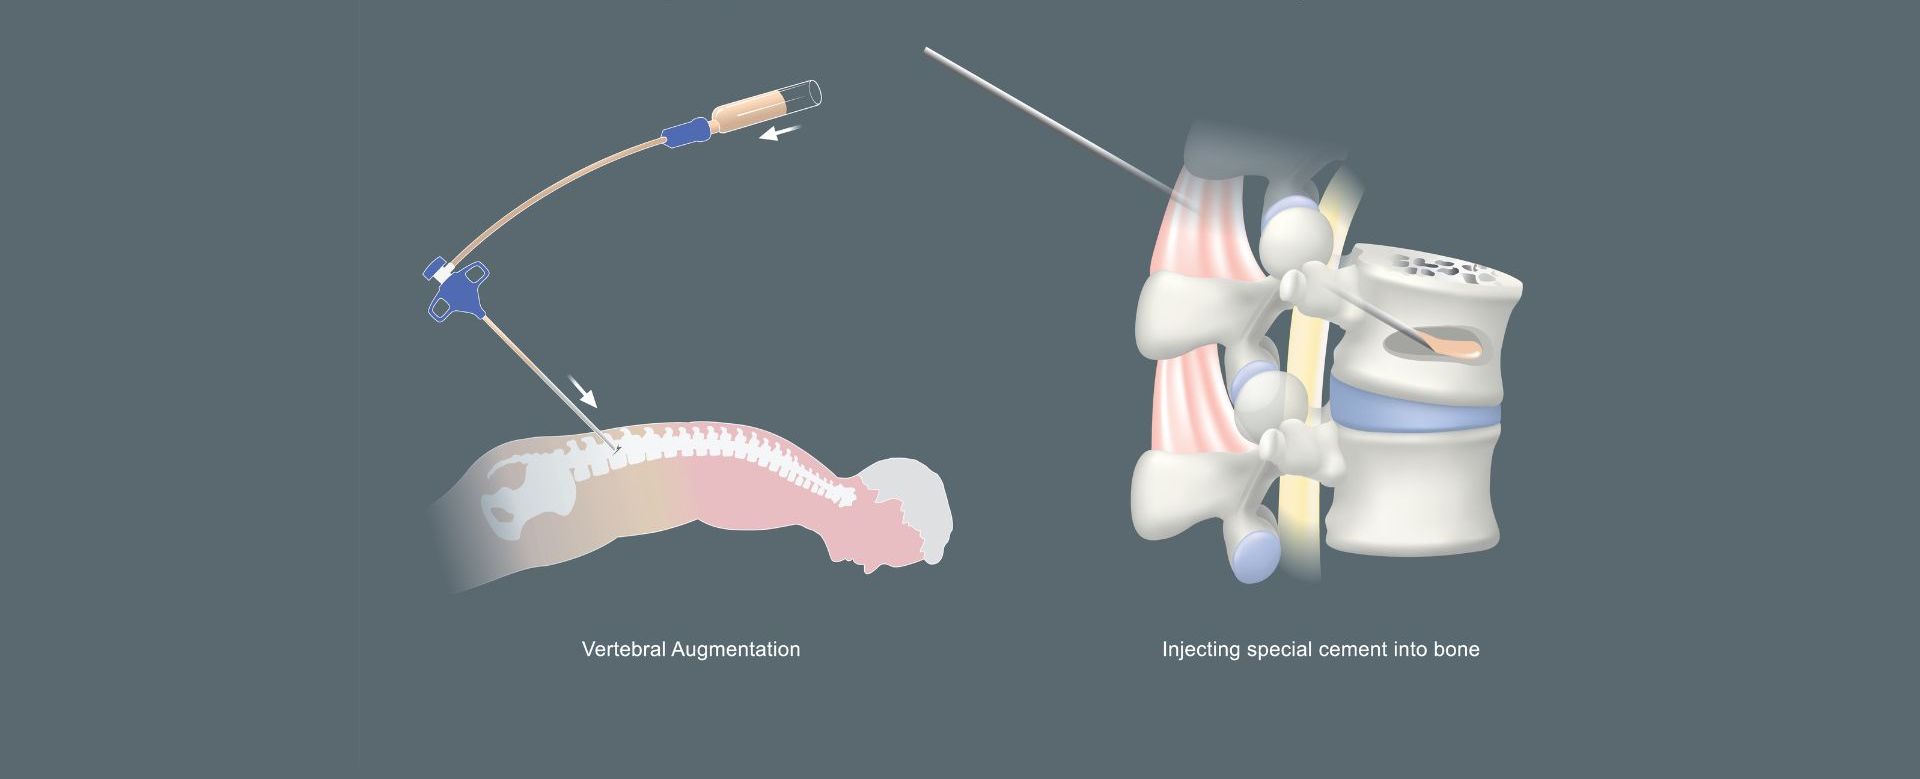

Είναι μια μη χειρουργική εφαρμογή η οποία πραγματοποιείται με ακτινοσκοπική καθοδήγηση και υπό τοπική αναισθησία και ελαφρά καταστολή. Ο ασθενής τοποθετείται σε πρηνή θέση (μπρούμυτα) και αφού γίνει πολύ προσεκτική αντισηψία της περιοχής, μια ειδική βελόνα προωθείται δια μέσω του αυχένα του σπονδύλου, μέσα στο σώμα του σπονδύλου που έχει υποστεί το κάταγμα. Η σωστή και ασφαλής προώθηση και τελική θέση της βελόνας ελέγχεται συνεχώς με λήψη ακτινοσκοπικών εικόνων σε προσθιοπίσθια και πλάγια θέση.

Μια μικρή ποσότητα ακρυλικού τσιμέντου προωθείται μέσα από τον αυλό της βελόνας, στο σπονδυλικό σώμα. Το ακρυλικό τσιμέντο είναι ένας τύπος ιατρικού τσιμέντου που χρησιμοποιείται εδώ και πολλά χρόνια σε διάφορες ορθοπαιδικές χειρουργικές επεμβάσεις. Όταν το τσιμέντο εγχύεται έχει τη μορφή οδοντόκρεμας και μόλις βρεθεί μέσα στο σπόνδυλο πήζει ταχύτατα. Μετά από λίγες ώρες από το τέλος της σπονδυλοπλαστικής, ο ασθενής είναι σε θέση να περπατήσει χωρίς πόνο και να πάει στο σπίτι του ακόμη και την ίδια μέρα (6,7,8,9)